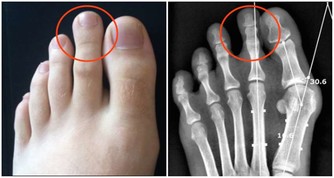

第七名:吃得過咸、吃高嘌呤涮菜冬天,人們都喜歡吃火鍋,但涮肉吃多了也會傷腎。

涮菜中如豆製品等是高嘌呤食物,而且涮肉的湯汁中嘌呤含量很高,

這些都會造成脾胃負擔過重,也會加重腎臟負擔。

高嘌呤、高脂肪、高熱量食物攝取過多,時間長了,再好的腎臟都會累。

第八名:海鮮就啤酒很多人喜歡就海鮮喝啤酒,不過如果邊吃海鮮邊喝啤酒,這種吃法也會傷及腎臟。

海鮮產品是高蛋白食物,含有嘌呤和苷酸成分,和啤酒混合在一起,會產生過多的尿酸和尿素氮等代謝物,

加重腎臟負擔,易導致高尿酸血症,甚至腎結石、尿毒癥。